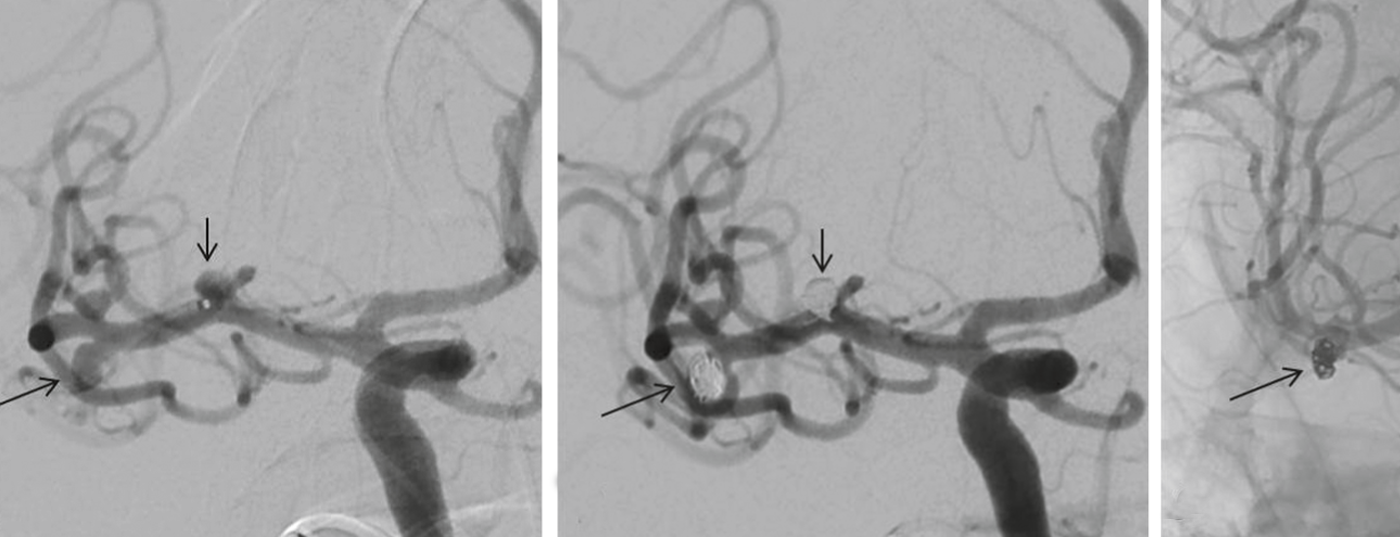

Eine aneurysmatische Subarachnoidalblutung (aSAB) ist mit hoher Mortalität und Morbidität vergesellschaftet. Nach initialer Stabilisierung des Patienten muss durch neurochirurgische und/oder endovaskuläre Therapieformen die Blutungsquelle ausgeschaltet werden. Aneurysmen, die für beide Therapie­optionen in Frage kommen, sollten bevorzugt endovaskulär ­behandelt werden. Dennoch eignet sich nicht jedes Aneurysma für die endovaskuläre Therapie und die chirurgischen Möglichkeiten haben bis heute einen klaren Stellenwert. Aufgrund des minimal-invasiven Charakters und der fortschreitenden Weiterentwicklung der endovaskulären Methode ist dennoch mit ­einer Zunahme dieser Therapieform zu rechnen. Die vorliegen­de Arbeit soll die Möglichkeiten beider Therapieoptionen vorstellen.